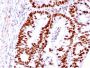

HCT116, MCF-7, A431 or HeLa cells. Colon Carcinoma.

Antibody applications

IF (verified)|IHC, FFPE (verified)|WB (verified)

IF (verified)|IHC (FFPE) (verified)|WB (verified)